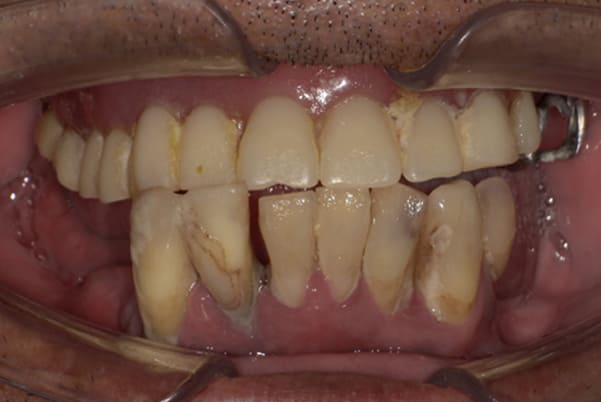

上前歯はブリッジの差し歯により根が折れ炎症を起こしお痛みのある状態でした。

原因は長期使用により下の義歯の歯が削れたことにより、下前歯が上前歯を突き上げ強い力が加わっていたことが根本的な原因と考えられます。

治療前は、奥歯が下がり、かみ合わせが乱れています。適切な入れ歯はそのままのかみ合わせで義歯を作るのではなく治療後のように、前歯から奥歯までのラインが真っすぐ揃った、かみ合わせの面を適切に付与し、よく咬め、残りの歯に負担がかからないかみ合わせとしました。

とにかく何も食べられないこと、人に会えないことから、なるべく早く何とかしたいとのご希望でした。

患者様とご相談の上、まず早急に上記を回復させるため、初診含め3度の来院でお食事ができ、見た目を回復できるように治療用義歯を作製、装着しました。

本来は、数本の上前歯の折れてしまって残せない歯は抜いてから歯肉の治癒を待ち、数か月後に型どりから作製になりますが、抜歯即時義歯といって、歯を抜く前に型、かみ合わせをとり、抜歯を行ったその日に上下の義歯を装着する特殊な治療法を用いたことで、10日後には治療用義歯をお口に装着することができ、お痛みもなくお食事ができ、ご友人とのお食事にも行けることが可能になりました。

本来、入れ歯作製は技工所と言って、義歯を作製する所に発送するため、作製には時間がかかりますが、院内に技工専用スペースを完備しており、長年、義歯治療において、技工も技術の習得してきましたので技工士さんではなく、かみ合わせの道具も私自身で院内で作製したことで、初診日の次の日にご来院いただきかみ合わせを採ることで、診断、型どり、かみ合わせ、装着まで10日という最短のご希望にこたえらた方です。